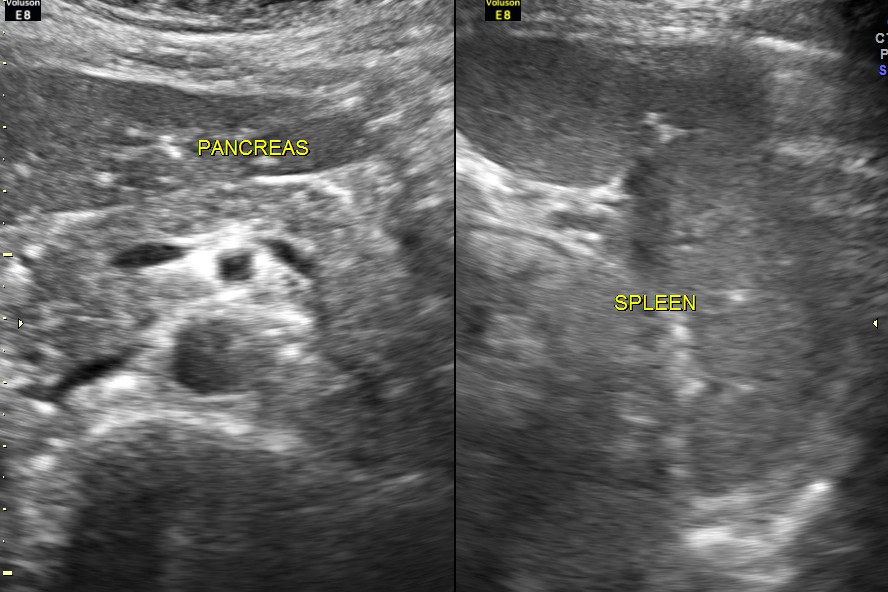

Ultrasound of the liver, gall bladder , pancreas and spleen revealed no abnormality.